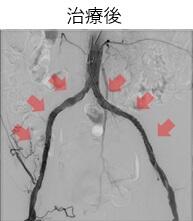

当院で血管内治療を行った閉塞性動脈硬化症の一例